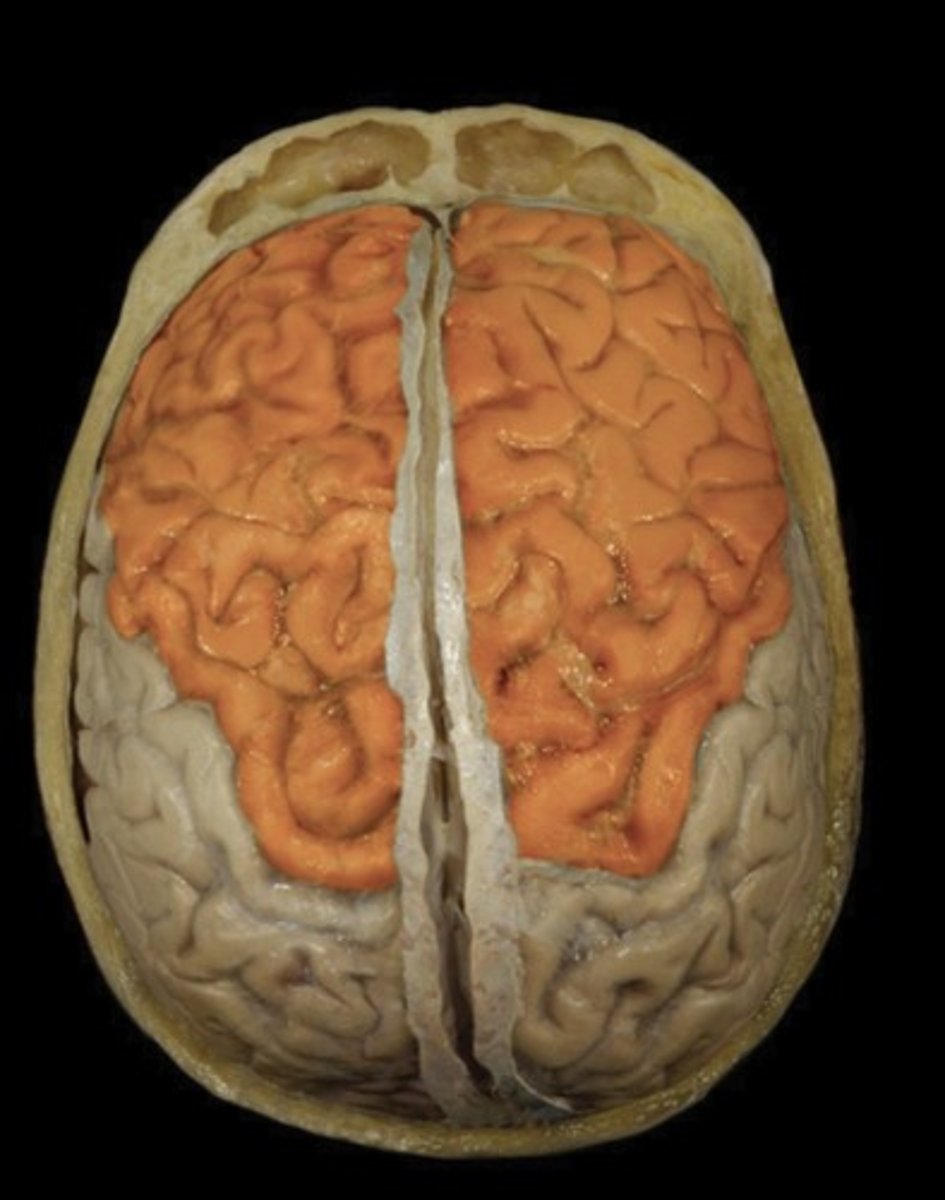

Frontal Lobe (superior view)

Name this structure

Occipital Lobe (superior view)

Name this structure